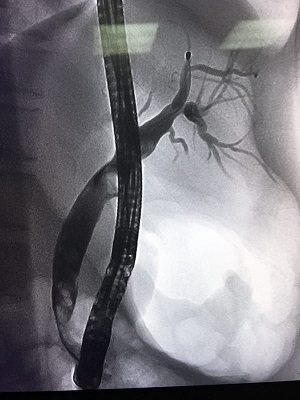

ERCP造影

ERCP取出膽總管結(jié)石